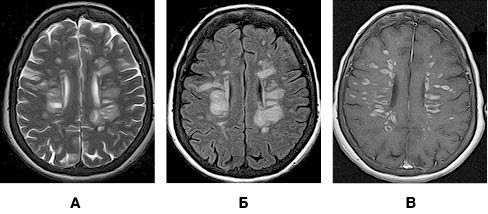

На рисунку 1 представлено МРТ-зображення головного мозку пацієнта з ГРЕМ у режимах Т2, Т2/Flair та Т1 із внутрішньовенним контрастуванням. Зокрема, візуалізуються двобічні вогнища округлої та овоїдної форми, гіперінтенсивні в режимах Т2 та Т2/Flair, які в більшості випадків накопичують контраст.

/images/nn257-1622023r1_.jpg)